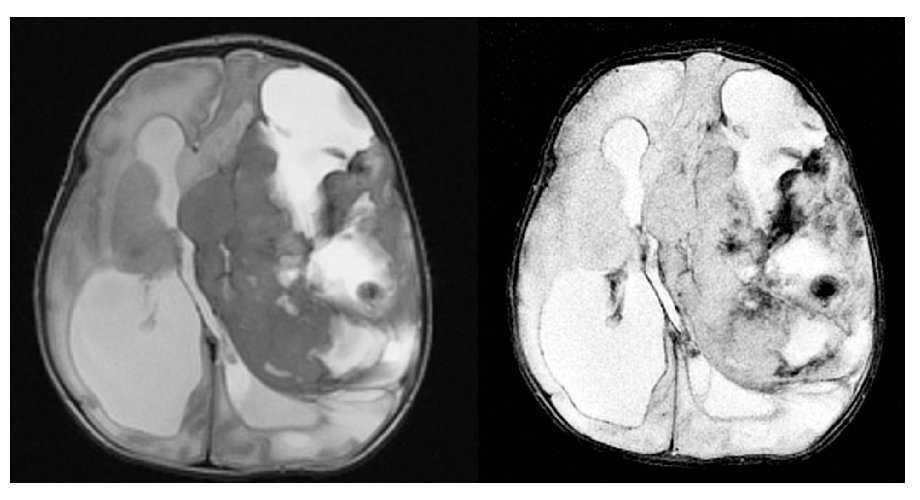

Fig. 3.